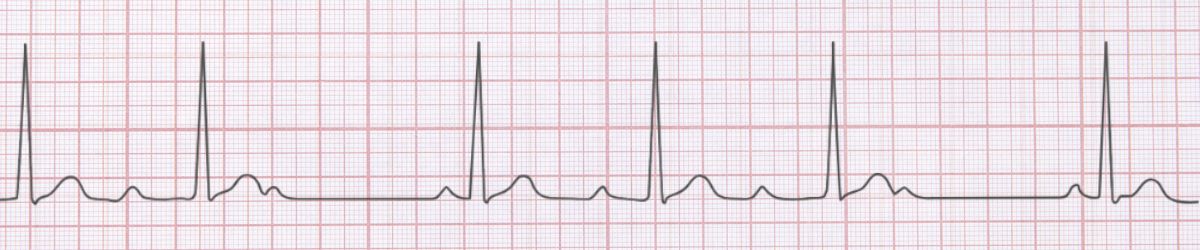

First Degree AV Block ECG Example

Figure 1: First Degree AV Block - Characteristic ECG Pattern

π Diagnostic ECG Criteria

- PR interval >0.20 seconds

- Every P wave conducted

- 1:1 AV conduction

- Regular rhythm

First Degree AV Block is characterized by pr interval >0.20 seconds and every p wave conducted. Usually benign, may indicate AV nodal disease, can progress to higher degrees Management priority: Monitor for progression, identify reversible causes (medications, ischemia) Key takeaway: Recognition and reassurance are the primary interventions needed